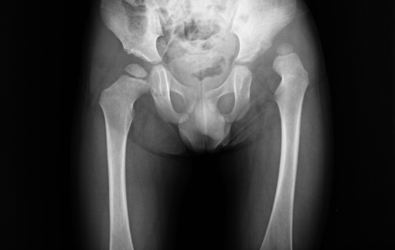

Προ-εγχειρητικά

Μετ-εγχειρητικά

Οι ακτινογραφίες απεικονίζουν περιστατικά με αναπτυξιακή δυσπλασία στα ισχία, τα οποία παρουσιάστηκαν στην κλινική μας μετά την ηλικία των τριών ετών. Πραγματοποιήθηκε χειρουργική επέμβαση από τον Δρ. Ζένιο για ανάταξη των ισχίων με οστεοτομία λεκάνης και μηριαίου.